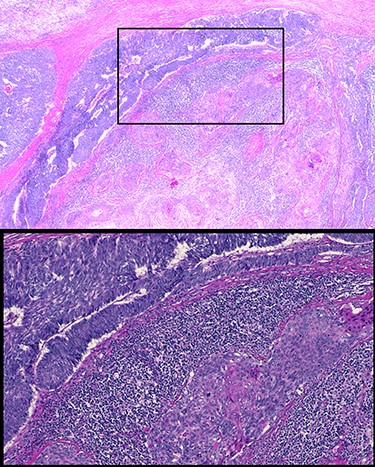

Sixty-three-year-old male was with the history of diabetes and hypertension who presented with 2 days of new onset, intermittent and non-pleuritic left-sided chest pain, with a few months of new onset exertional dyspnea. Chest X-ray showed a convex shaped mass at the left hilum. Chest CT angiography revealed a 5.6 × 7.1 × 5.4 cm hypodense mass in the anterior mediastinum involving the adjacent anterior medial left upper lobe, and adjacent mildly enlarged aorticopulmonary window lymph nodes (Fig. 1). PET scan demonstrated a hypermetabolic anterior mediastinal mass adjacent to medial left upper lobe highly suggestive of malignancy (Fig. 2). Ultrasound-guided core needle biopsy showed nests of small cells with peripheral palisading and focal abrupt transition to squamous cell, consistent with basaloid carcinoma of thymic gland. Immunostainings of the tumor cells were positive for cytokeratin AE1/AE3, cytokeratin CK904, p63 and p40.

Pre-operative PET scan demonstrating a hypermetabolic anterior mediastinal mass.